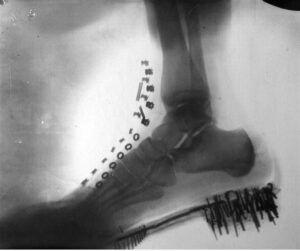

Тесла продолжил да се истражува во областа на рендгенските зраци. Спроведувал сопствени експерименти и создал вакуумска цевка со висока енергија која работела преку излез од Теслината калемка — неговото најпознато изумување. Тој ги нарекувал „сенковни слики“ и ги изработувал користејќи го најлесниот модел што можел да го најде — самиот себе. Рендгенските слики од неговото стапало (со металните делови на чевелот уште видливи) и од неговата рака претставуваат голем доказ за неговата работа.

Но придонесите на Тесла во радиологијата не завршиле тука. Тој брзо ги посочил и медицинските придобивки од рендгенот. Забележувајќи дека зраците различно ги прикажуваат погустите органи во споредба со понејасните, Тесла објаснил како технологијата може да се користи за наоѓање туѓи предмети во телото или за откривање белодробни болести.